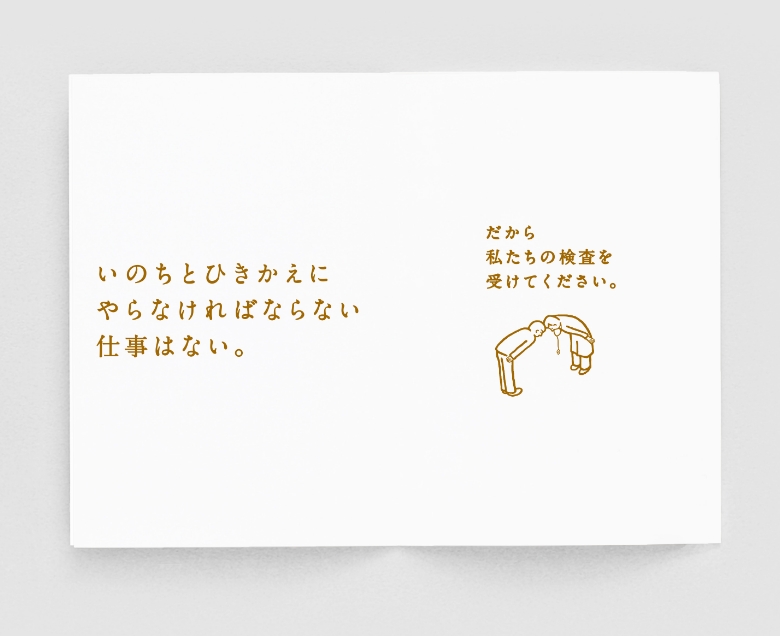

FUJITAIIN

-

Client : Fujita-iin

-

Creative Director : Shunichi Iwasaki

-

Art Director : Yoshihiro Kobayashi

-

Designer : Yoshihiro Kobayashi

MORE >